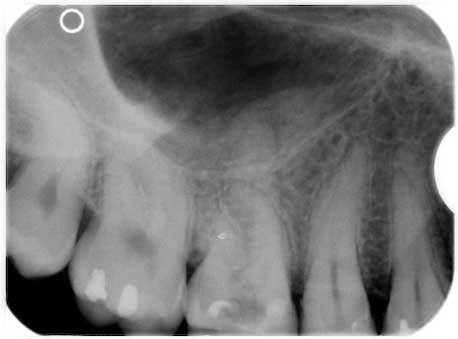

Koryphäenkiller einmal anders